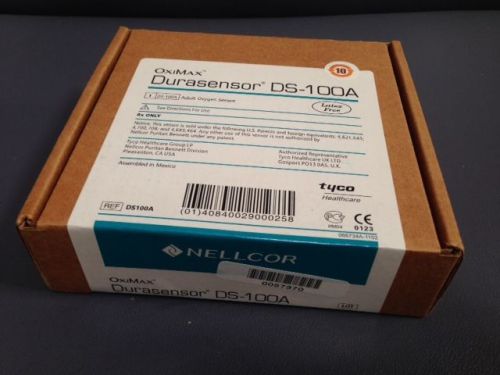

1 Adult SPO2 Finger Sensor Nellcor DS100A , by Covidien - New Sealed Box

Nellcor DS100A-1 Adult SPO2 Finger Sensor, by Covidien - New Sealed Box